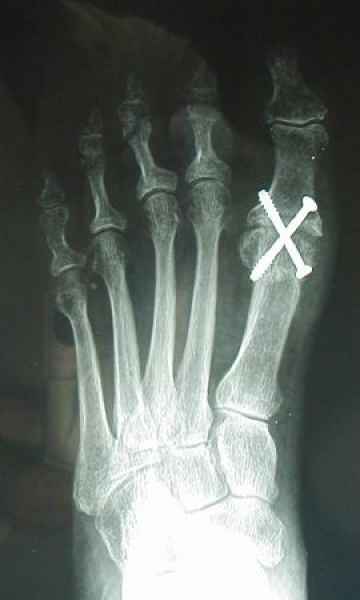

Tanto la estructura del pie como su funcionalismo que es la marcha, pueden ser asiento y manifestación respectivamente de alteraciones locales ó sistémicas, por lo que su cuidadoso examen resulta de extrema utilidad diagnóstica.

Dr. Juan Pablo Peralta, Ortepedia y Traumatología, Especialista en pies, Instituto Gamma